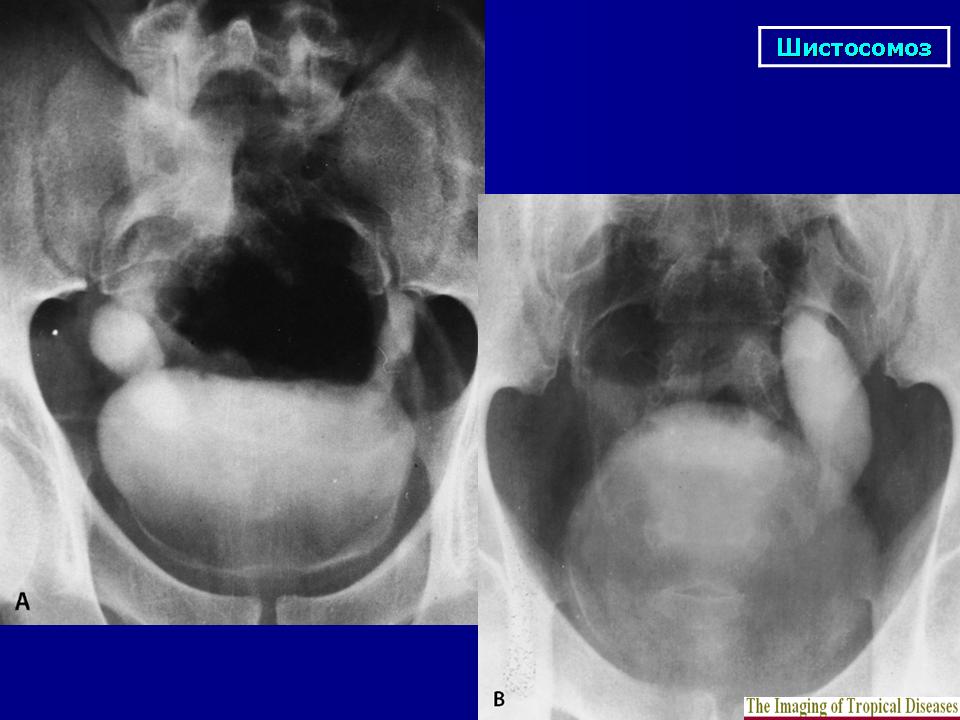

Бильгарциоз (Schistosomiasis) мочевого пузыря